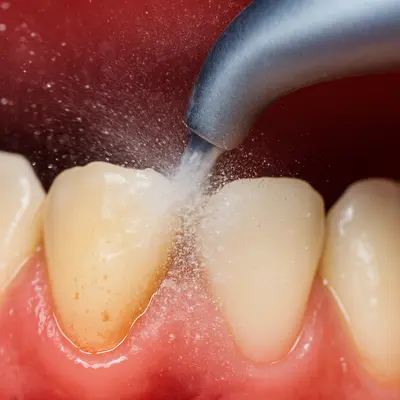

رعایت بهداشت دهان و دندان، مسواکزدن منظم با خمیردندانهای حاوی فلوراید، و استفاده از خمیردندان ضدحساسیت نقش مهمی در کاهش تحریک عصب دندان دارند.

به بیماران توصیه میشود پس از هر وعدهٔ غذایی، مخصوصاً بعد از خوردن مواد شیرین، حتماً از نخ دندان استفاده کنند تا ذرات قند در فواصل دندانی باقی نماند.

انجام جرمگیری دورهای و معاینهٔ منظم توسط دندانپزشک نیز به شناسایی زودهنگام پوسیدگیهای سطحی کمک میکند.

در واقع، برای جلوگیری از درد دندان بعد از خوردن شیرینی باید مینای دندان را تقویت و محیط دهان را از تجمع قند و باکتری پاک نگه داشت.

پرهیز از خوردن مکرر مواد قندی، استفاده از دهانشویههای حاوی فلوراید و نوشیدن آب بعد از مصرف شیرینیها از سادهترین و مؤثرترین روشهای پیشگیری محسوب میشوند.

در قدم اول، باید با رعایت دقیق بهداشت دهان و دندان جلوی پیشرفت آسیب را بگیرید. مسواکزدن دو بار در روز، استفاده از نخ دندان بعد از غذا، و انتخاب خمیردندان ضدحساسیت، میتواند درد را کاهش دهد و از تحریک بیشتر عصب جلوگیری کند. انجام جرمگیری دورهای و مراجعهٔ منظم به دندانپزشک نیز از تجمع باکتریها و پوسیدگیهای پنهان جلوگیری میکند.